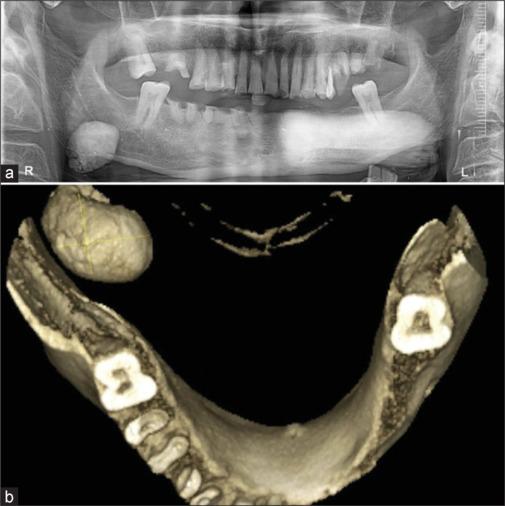

The sialolith is a calcified mass resulting from the crystallization of salivary solute made up of calcium phosphates such as hydroxyapatite and octacalcium phosphate with yellowish discoloration and different shapes and sizes in the range of 1-2 cm normally, while occurrence of large sialolithiasis is rare, with literature showing sizes from 3.5 cm to 7 cm noted till date. About 80% of sialolithiasis occurs in submandibular glands and 20% in parotid gland and <1% is seen with sublingual gland. For small sialolithiasis and for superficially located sialolithiasis at ductal regions, conservative management is performed. However, for larger sialolithiasis, surgical management is mandatory which includes various methods such as transoral sialolithotomy, laser techniques, and sialendoscopy-assisted techniques. Complete excision of salivary gland is recommended for large, multiple, and recurrent cases of sialolith. In the present study, we have presented the unusual-sized rare case of salivary gland stone found in submandibular salivary gland and not in ductal region which was mimicking an osteoma on OPG and discuss the review of literature. This giant sialolith was managed with extraoral submandibular approach followed by TOTO removal of the sialolith which measured about 38 g in weight and 28 mm in size. Present sialolith was the rarest till date with heavyweight of about 38 g and 28 mm in size. Even the conventional method is sufficient to excise the sialolith when other modalities are not available. Chronic sialolith is common in old male patients and shows positive correlation with chronic smoking.

涎石是由唾液溶质结晶形成的钙化团块,其主要成分是磷酸钙,如羟基磷灰石和磷酸八钙,通常呈淡黄色,形状和大小各异,一般在1 - 2厘米范围内,而大涎石病的发生较为罕见,文献记载至今发现的最大尺寸为3.5厘米至7厘米。约80%的涎石病发生于下颌下腺,20%发生于腮腺,舌下腺发病<1%。对于小涎石病以及导管区域浅表性涎石病,采取保守治疗。然而,对于较大的涎石病,则必须进行手术治疗,包括经口涎石切除术、激光技术和涎腺内镜辅助技术等多种方法。对于大的、多发的和复发性涎石病例,建议完整切除涎腺。在本研究中,我们报告了一例罕见的、尺寸异常的涎腺结石病例,该结石位于下颌下涎腺而非导管区域,在全景片上类似骨瘤,并对相关文献进行了综述。该巨大涎石采用口外下颌下入路,随后通过TOTO法取出,涎石重量约38克,尺寸为28毫米。目前的涎石是迄今为止最罕见的,重量约38克,尺寸为28毫米。当没有其他方法可用时,传统方法也足以切除涎石。慢性涎石在老年男性患者中较为常见,且与长期吸烟呈正相关。